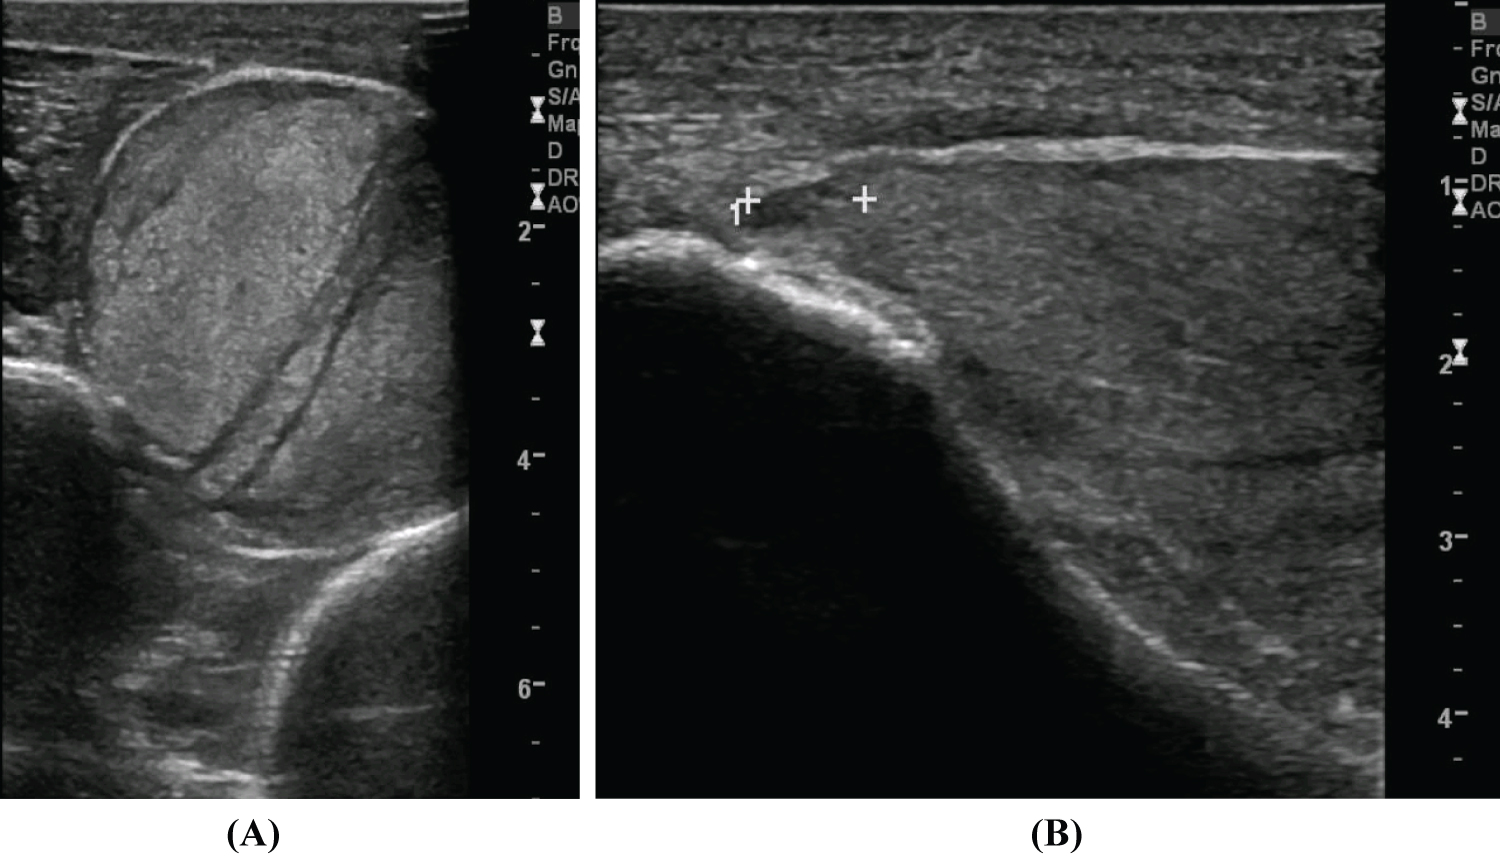

During hospitalization the patient maintained inability to dorsiflex his right ankle and extend hallux and toes. A rehabilitation program was initiated consisting of lower extremity muscle strengthening, articular mobilization and gait training. Due to right footdrop interfering with walking, an Ankle-Foot Orthosis (AFO) (Boxia®) was prescribed. Control CT scan revealed a large expansive heterogeneous area in the muscle plane of the external aspect of the right leg, encompassing the muscles and tendons of tibialis anterior, extensor hallucis longus and extensor digitorum longus, related to muscle necrosis, consequent to the compartment syndrome (Figure 3A and Figure 3B).

Figure 3: Leg TC Scan. A large expansive heterogeneous area in the muscle plane of the external aspect of the right leg, encompassing the muscles and tendons of tibialis anterior and long extensors of the fingers and hallux, related to evolving muscle necrosis, consequent to the compartment syndrome (A) Coronal plane; (B) Transverse plane. View Figure 3